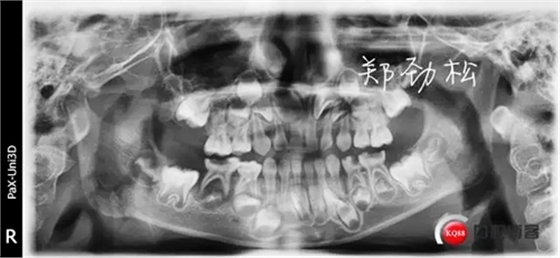

我的病例二 8E深齲導致的根尖炎

常規(guī)的開髓擴根后vitapex糊劑充填,可見近中根有明顯的糊劑超充。